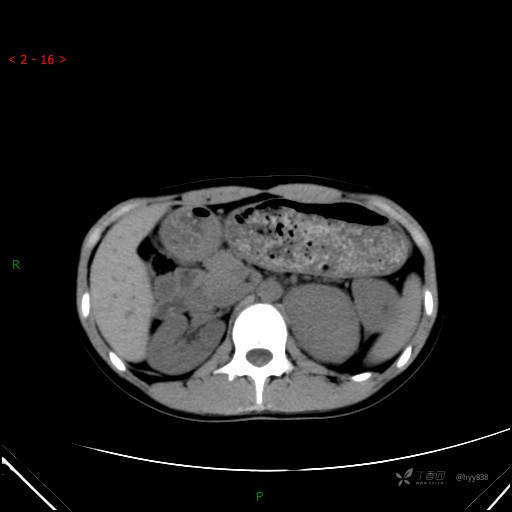

腹部CT平扫